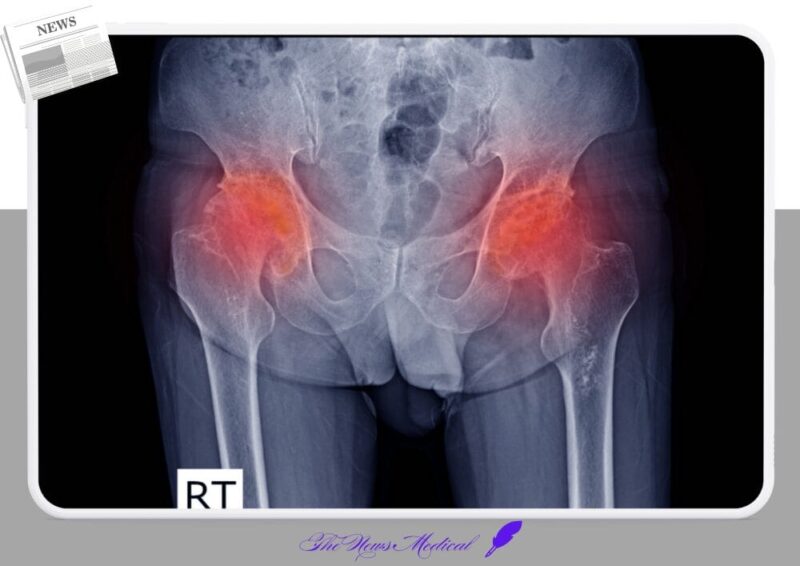

발달성 고관절 이형성증은 태어날 때부터 혹은 출생 후 성장 과정에서 고관절(엉덩이 관절)의 비정상적인 발달로 인해 대퇴골 머리(허벅지뼈 윗부분)가 골반의 비구(관절을 이루는 오목한 부분)에 제대로 안착하지 못하거나, 불안정하게 위치하는 상태를 말한다. 이는 완전한 탈구부터 아탈구, 또는 비구의 발달 부전까지 다양한 형태로 나타난다.

만약 보조기 착용으로 고관절이 안정화되지 않거나, 진단 시기가 늦어져 이미 고관절이 심하게 탈구된 경우에는 ‘수술적 정복술’이 필요하다. 수술적 정복술은 크게 도수 정복술과 관혈적 정복술로 나뉜다. 도수 정복술은 전신 마취 하에 의사가 손으로 대퇴골 머리를 비구에 맞춘 후, 석고 고정으로 일정 기간 유지하는 방법이다. 반면, 관혈적 정복술은 피부를 절개하여 직접 고관절을 노출시킨 후, 탈구된 대퇴골 머리를 비구에 정확히 맞추고 필요에 따라 비구 성형술이나 대퇴골 절골술 등을 시행하여 고관절의 안정성을 확보하는 방법이다.